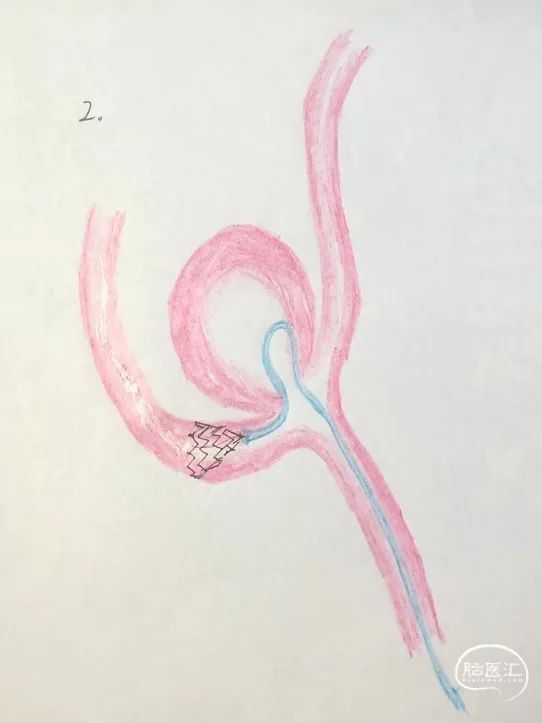

支架释放过程:固定支架推送导丝,回撤45°微导管,最终完成3.0mm*24mm Atlas支架的释放。

再将该微导管送回,穿过支架网眼,送入动脉瘤瘤腔内。

第一个圈首先选用12mm*40cm弹簧圈顺利成篮。此时,部分弹簧圈突入同侧A2段。

将3.0mm*21mm Atlas支架释放到同侧大脑前动脉A2段,近端衔接在第一个支架的体部,使两个支架形成T型结构,然后将弹簧圈解脱。